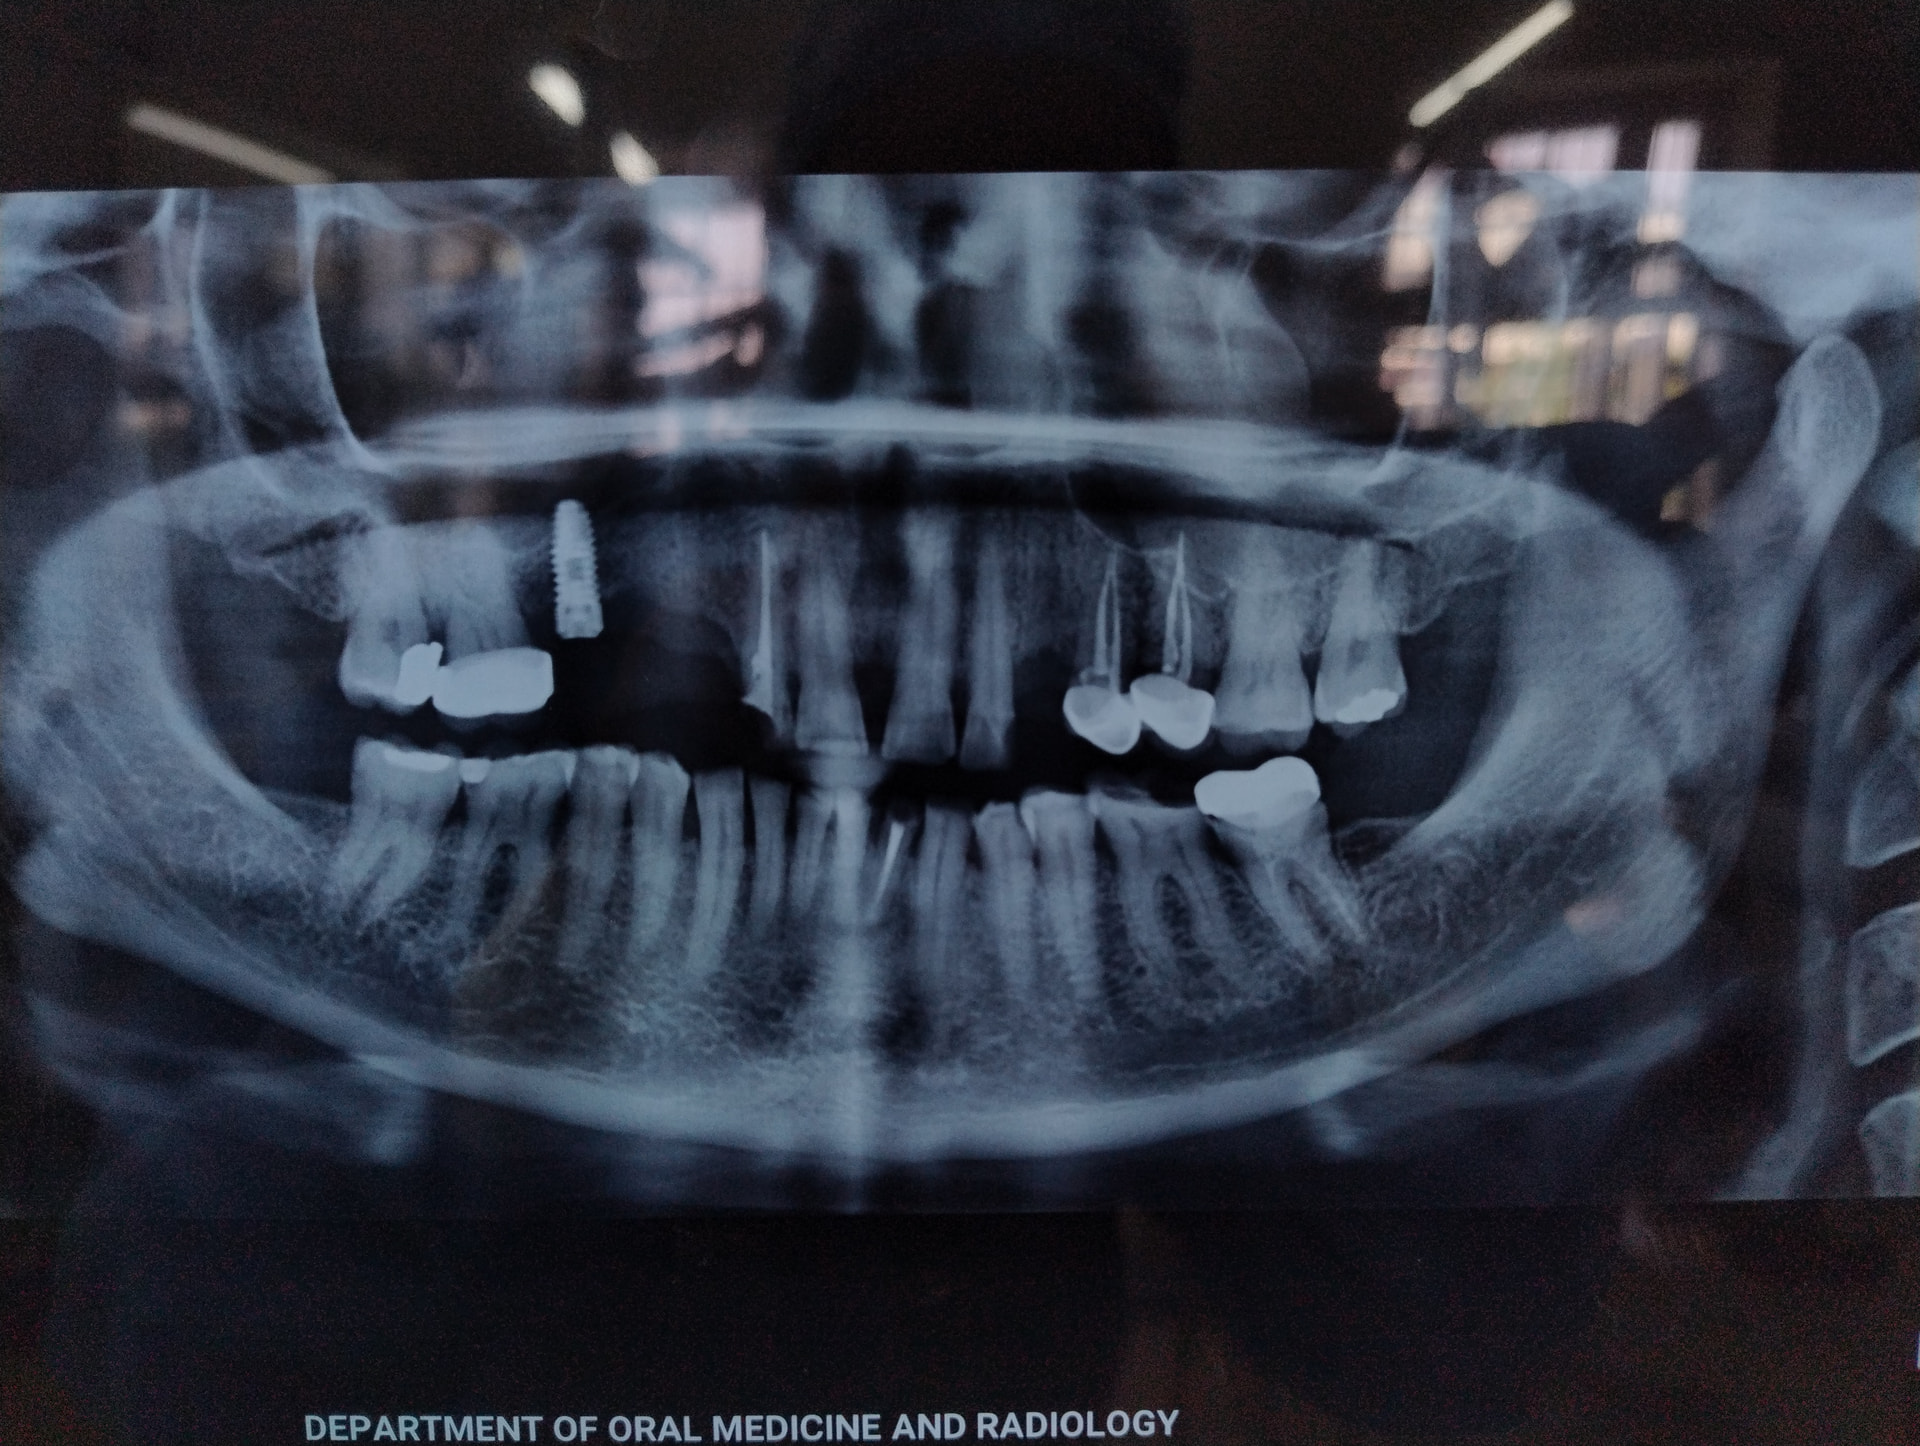

Implant identification

Implant was placed around 6 years back in India. Need help in identifying the implant.

The shape on the radiograph appears similar to a Neoss but if you can uncover and remove the cover screw a photo of the connection can help confirm…